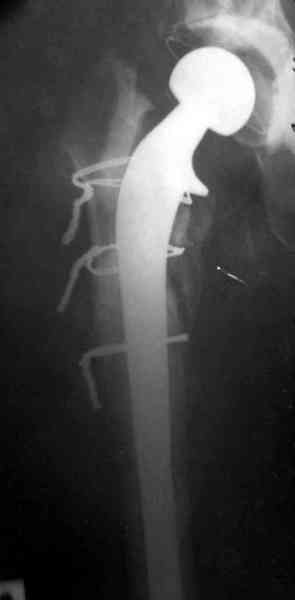

Для спейсера в бедро использовал старый длинный бедренний компонент меньшего диаметра, облепленный со всех сторон цементом с антибиотиком.

Наглухо ушитая рана с дренажом зажила первично, после чего с больной потерял контакт, и только недавно, через 8 лет я осмотрел её. Она без проблем нагружает на конечность и передвигается с помощью трости. От окончательной операции по реконструкции отказывается, довольная результатом.

Имеются литературные данные, когда спейсер держали не более 6 месяцев, но этот случай бьет все рекорды, может быть для наших людей, обременных финансовыми трудностями, нужна другая шкала оценки сроков нахождения спейсеров.

и последние снимки.